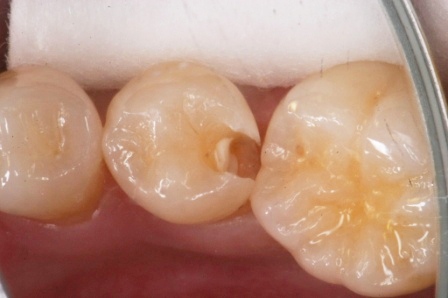

下顎7番の頬側歯茎部カリエスの原因 2025.06.04